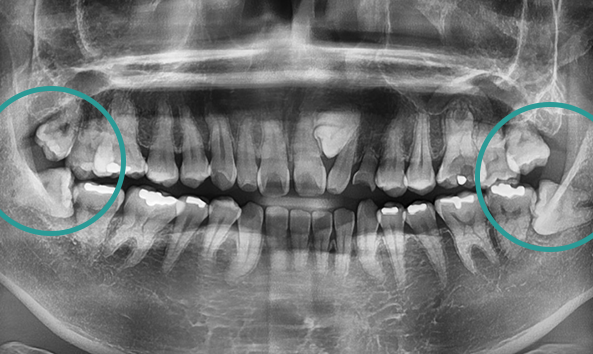

골치 아픈 사랑니, 대학병원 가지 않으셔도 됩니다.

사랑니는 기형적으로 맹출되거나

잇몸 속에 매복되는 경우가 많아 발치가 까다로울 수 있습니다.

특히, 인접 치아를 손상시키지 않고 신경을 보호하며 발치하려면

전문적인 노하우가 필수입니다. 그래서 사랑니 발치는 많은 고민과 망설임을 동반하는

어려운 선택이 될 수 있습니다. 올디플란트치과는 이런 걱정을 덜어드릴 자신이 있습니다.

사랑니 발치를 위해 치과를 찾아 헤매고 계신가요?

매복 사랑니는 신경과 가까워 발치 시

신경 손상의 위험이 높아

일부 동네 치과에서는 치료를 권하지 않기도 합니다.

하지만 올디플란트치과는

대학병원 가기 전에 방문하는 치과로 유명하며,

타원에서 발치하지 못한 케이스도

책임지고 해결해드리고 있습니다.